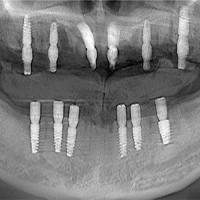

全牙列缺損修復病例

發布于 2025-10-24